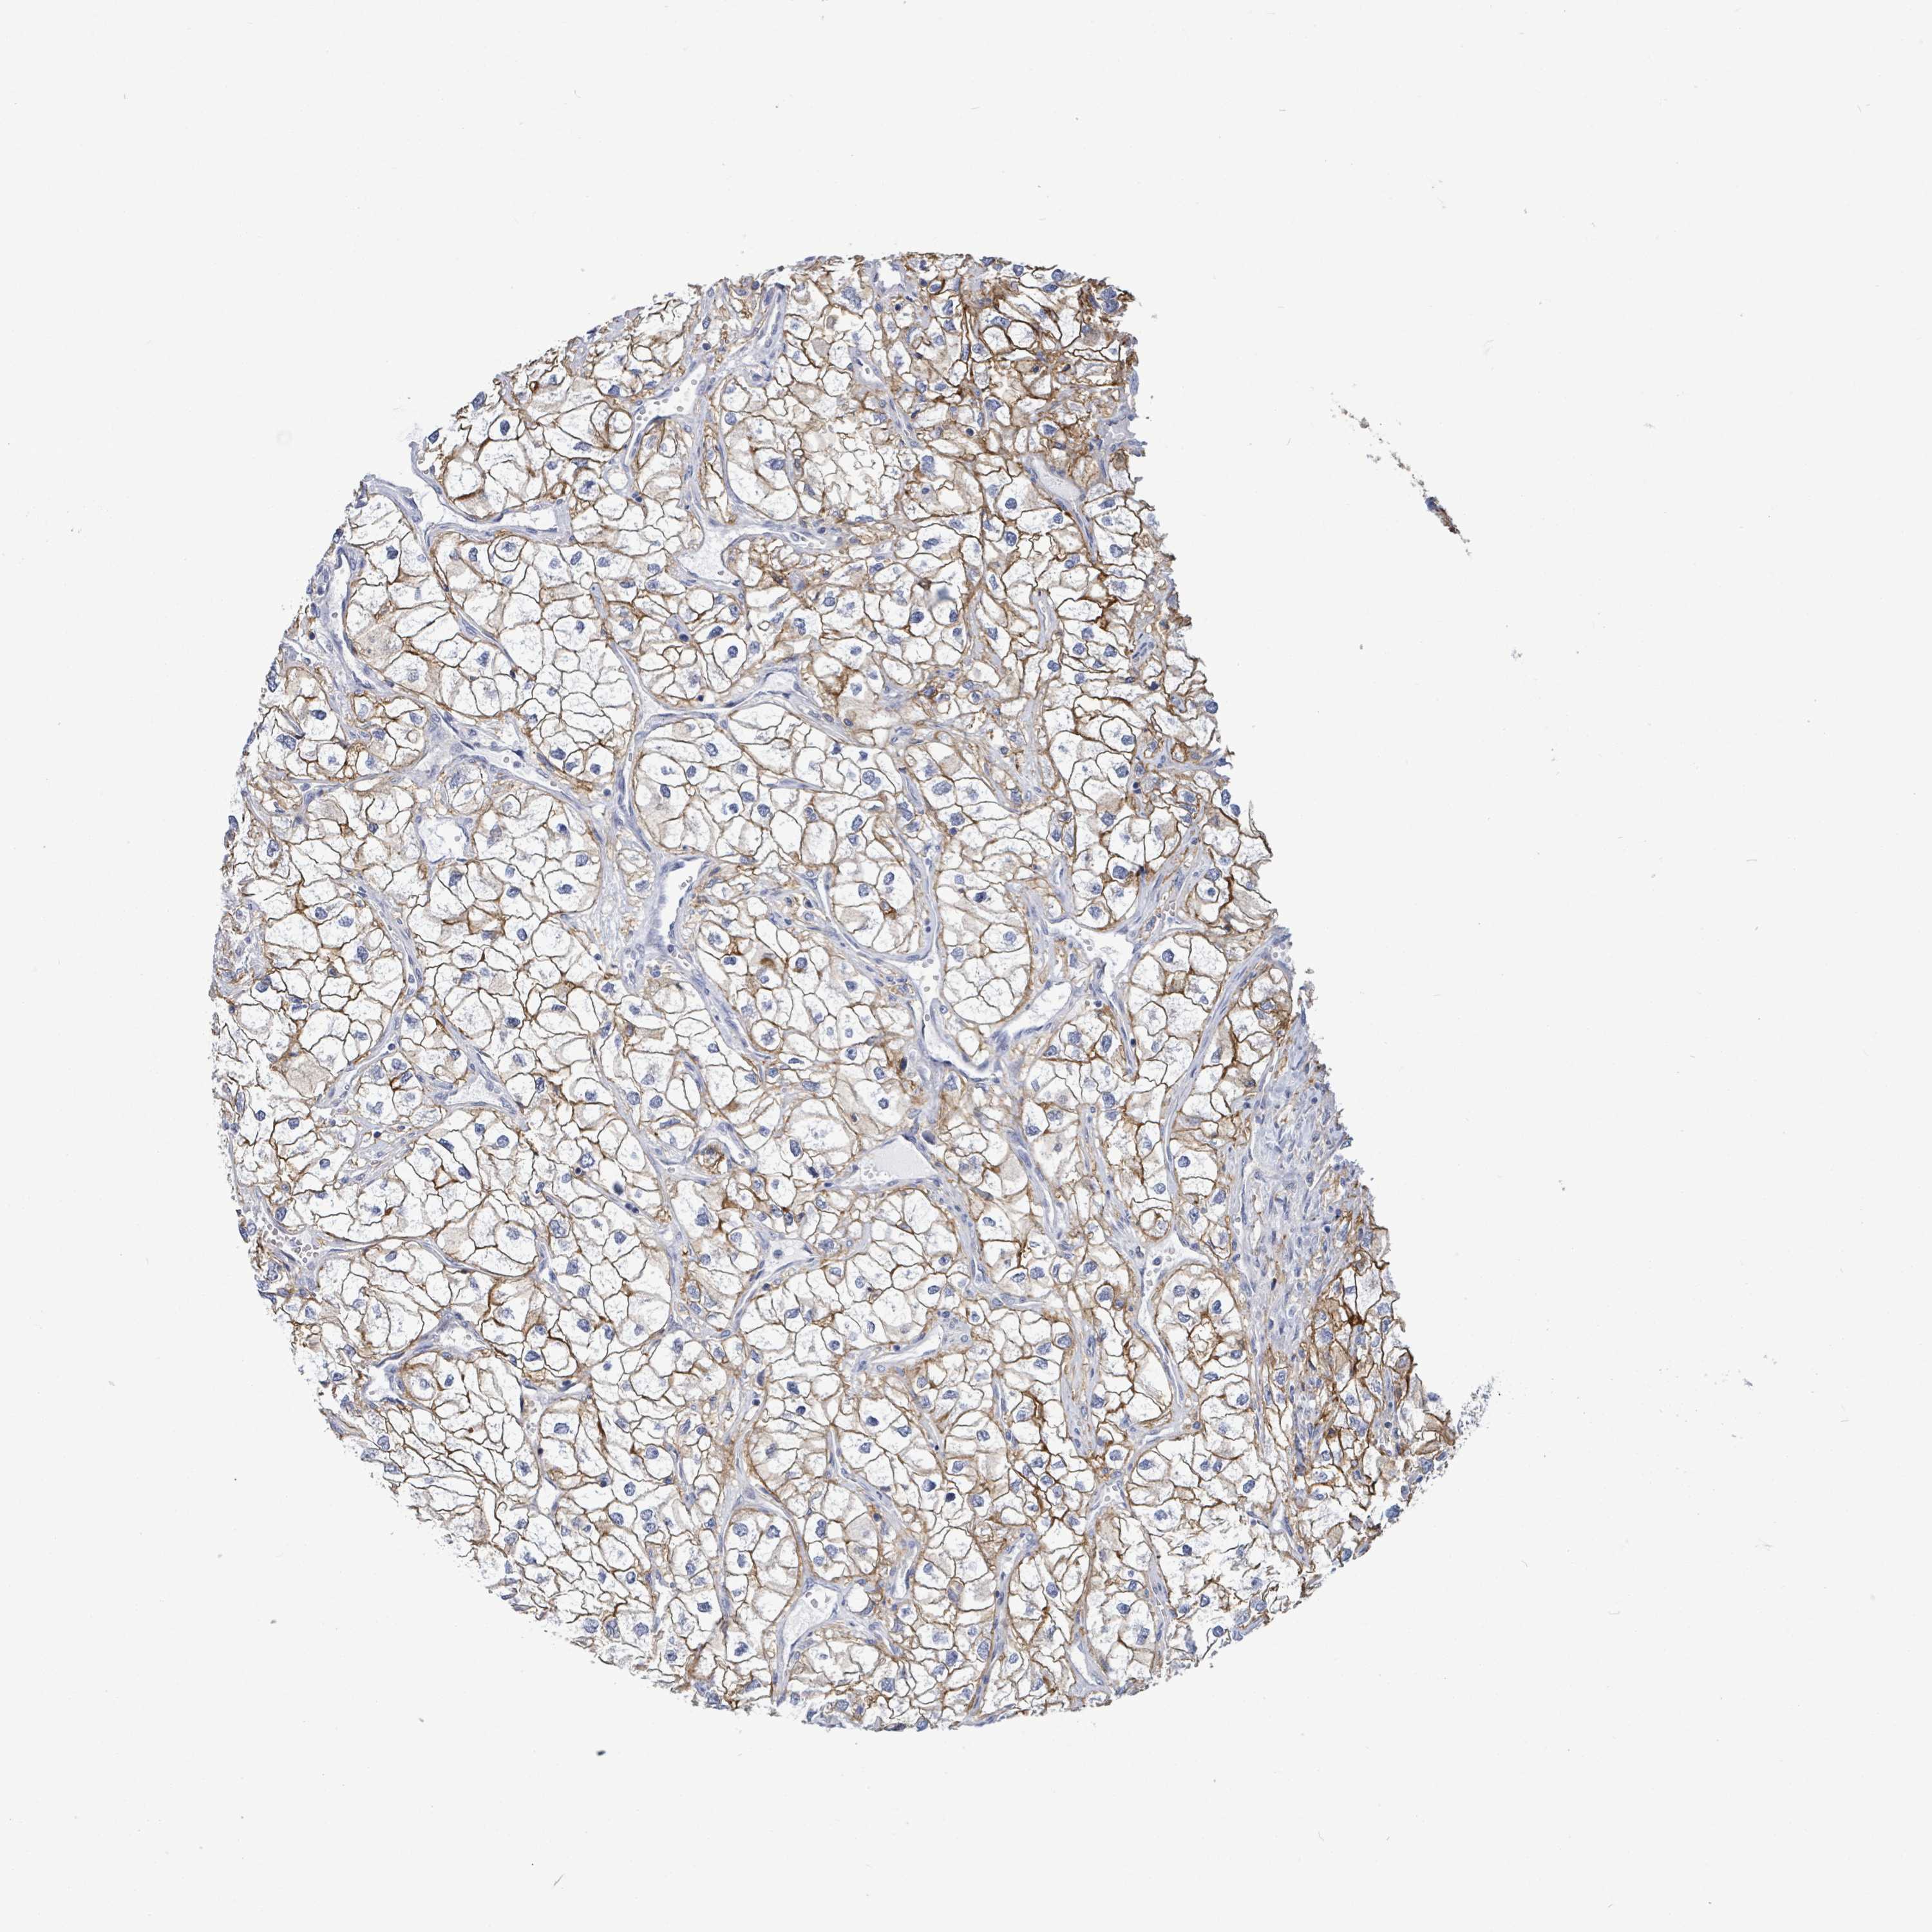

CANCER RENAL CANCER Show tissue menu

KICH TCGA KIRC TCGA KIRC VALIDATION KIRP TCGA PROTEIN RCC CPTAC PROTEIN EXPRESSION

Renal cancer

Kidney renal clear cell carcinoma